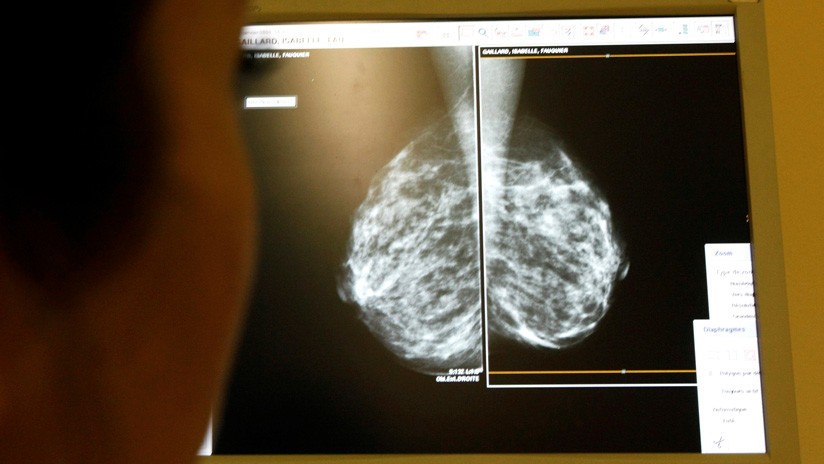

Una mala evaluación médica le cambió la vida a una mujer al ser diagnosticada con cáncer por error y sometida a 30 sesiones de quimioterapia sin necesitarlas. Como consecuencia, desarrolló una masa gigantesca que ameritó la amputación de una pierna y parte de la cadera.

La mujer había sido atendida en el Hospital General de Zona número 50 del Instituto Mexicano del Seguro Social (IMSS) en San Luis Potosí, México. Allí, le indicaron que padecía un cáncer agresivo, no operable, y que solo le quedaban seis meses de vida, reseñó Noticieros Televisa.

El tratamiento oncológico empeoró de forma dramática la salud de la paciente. El tumor benigno que inicialmente medía dos centímetros creció asombrosamente hasta a pesar 10 kilos. El enorme tejido estaba ubicado en el hueso ilíaco, en la cadera.

Todo comenzó en abril de 2017, cuando la mujer acudió a hospital por sufrir una fuerte contractura e intensos dolores en piernas, glúteos y espalda. Sin indicarle algún examen, lo médicos consideraron que el dolor era provocado por una presión en el nervio ciático, publicó Milenio.

Luego de 4 meses de tratamiento en casa y sin ver mejoría, la paciente volvió al centro de salud. Esta vez, le diagnosticaron cáncer por error: tendría un tumor de células gigantes de hueso que no se podía extirpar mediante cirugía. Le indicaron 30 sesiones de quimioterapia que duraron seis meses.

En mayo de 2018, en busca de una segunda opinión, un nuevo chequeo reveló la verdad: los doctores se equivocaron, la mujer nunca tuvo cáncer. Pero, debido al gran tamaño que había alcanzado la tumoración, era necesario amputarle de la cintura para abajo.